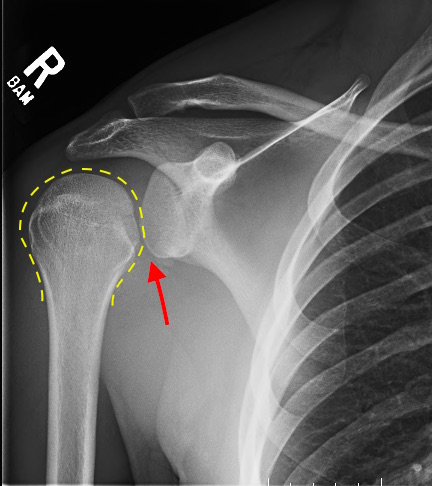

Рентген плеча: примеры снимков и их расшифровка